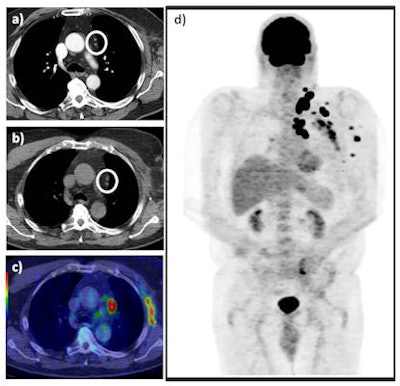

In the right hands, PET/CT has a significant clinical impact on management decisions in more than 40% of patients with recurrent stage III/IV malignant melanoma (MM) by detecting additional sites of distant metastatic disease and characterizing indeterminate CT findings, U.K. researchers have found.

"FDG PET/CT (18F-fluorodeoxyglucose positron emission tomography-CT) is an effective tool in recurrent stage III/IV malignant melanoma," noted Dr. Manil Subesinghe and colleagues from the department of nuclear medicine, Leeds Teaching Hospitals National Health Service (NHS) Trust."Effective use of FDG PET/CT is via referral from the specialist skin cancer multidisciplinary team."

A total of 51 FDG PET/CT examinations on 45 patients met the study's criteria. The procedure had a major clinical impact in 21 cases (41.2%), of which 18 examinations were performed in patients with proven or suspected stage IV MM. FDG PET/CT had a minor impact in 23 cases (45.1%), and there were five false-positive cases (9.8%) and two false-negative cases (3.9%), reported Subesinghe, who provides regular specialist radiology support for the Leeds Specialist Skin Cancer MDT Centre.